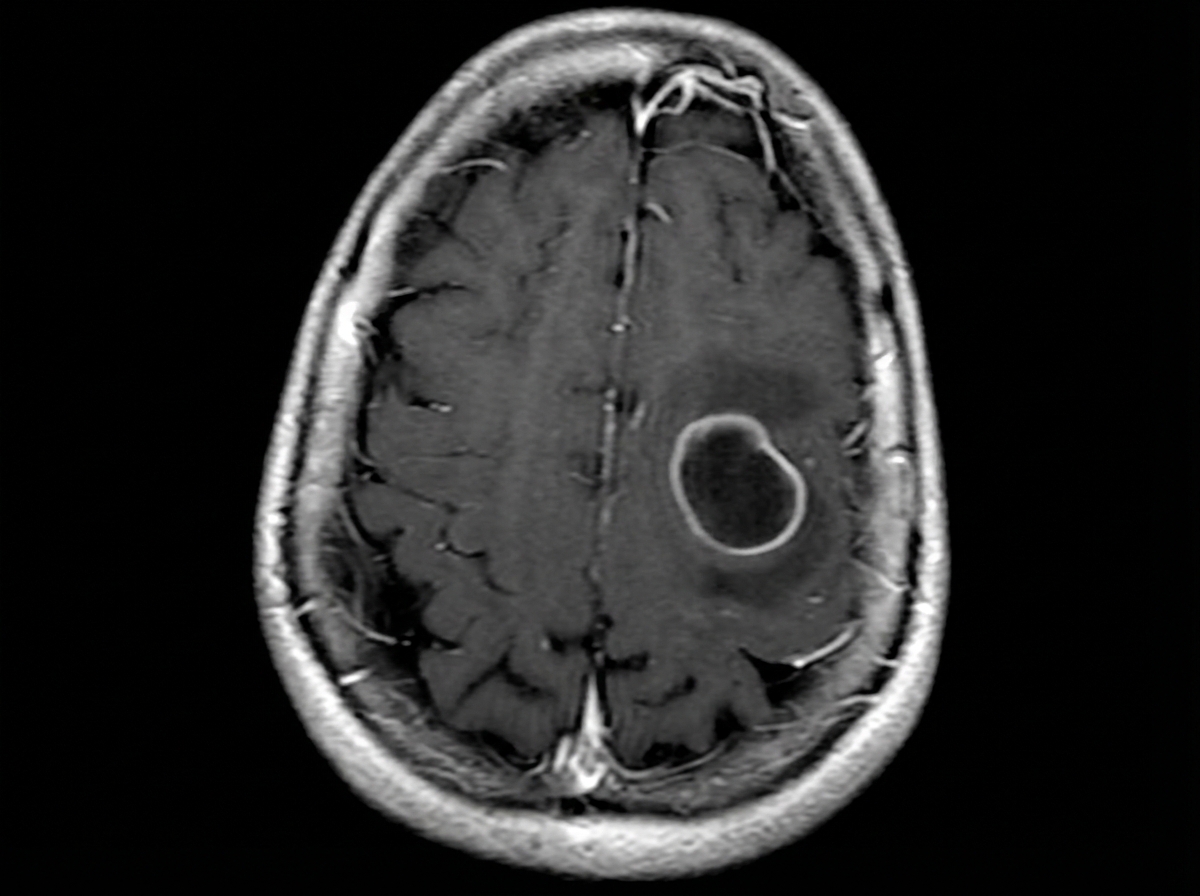

A 61-year-old woman visits the clinic with a complaint of new-onset episodic abnormal body movements. She says her husband noticed it twice in the past week. There were jerky movements for roughly 15 seconds during her last episode. She denies any recent trauma or fever. Her vital signs include: blood pressure 114/74 mm Hg, pulse 81/min, temperature 36.7°C (98.1°F) and respiratory rate 10/min. On physical examination, there is no evidence of focal neurological deficits. A basic metabolic panel is ordered which shows: Sodium 141 mEq/L Potassium 5.1 mEq/L Chloride 101 mEq/L Bicarbonate 24 mEq/L Albumin 4.3 mg/dL Urea nitrogen 11 mg/dL Creatinine 1.0 mg/dL Uric Acid 6.8 mg/dL Calcium 8.9 mg/dL Glucose 111 mg/dL A contrast magnetic resonance imaging (MRI) of the head is shown in the provided image. Which of the following cells is the origin of the lesion seen in this patient’s MRI?